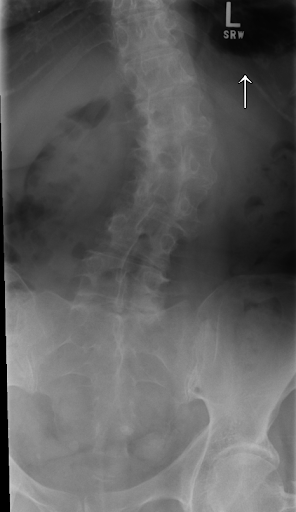

I enjoy the 3D Spine Simulator. This review helpful to know about spine.